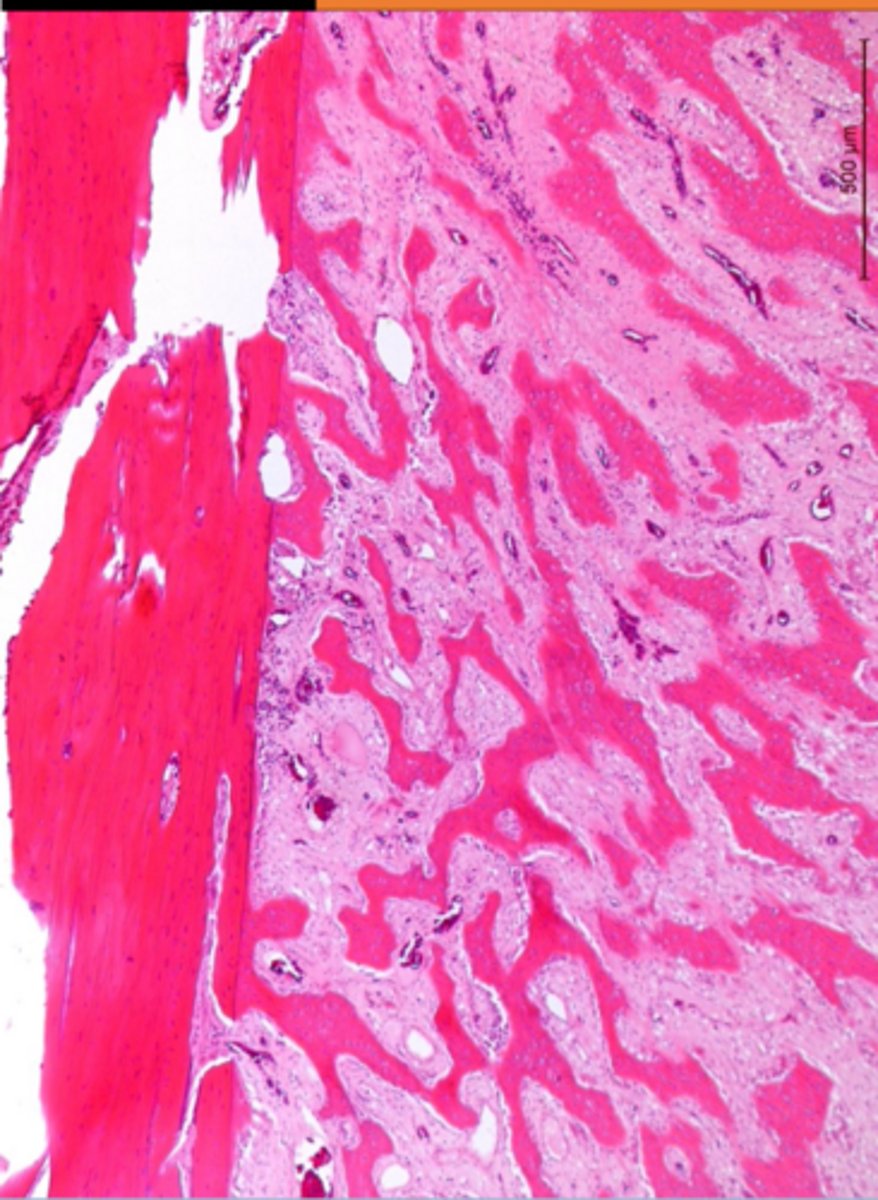

Which side is the callus formation?

R - callus formation

L - cortical bone